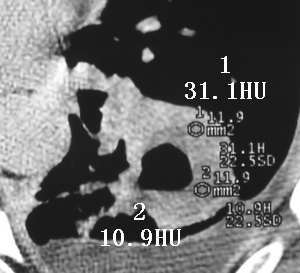

以下是引用sdqzwyx在2005-11-7 19:59:00的发言:[br]双肺弥漫大小不等的粟粒状结节影;肺纹理走行失去自然,粗细不均,边缘不规则,小叶间隔增厚;左上肺示不规则形致密影,从斑块边缘向周围伸出长短不一的致密索条影,临近的血管、支气管和叶间胸膜等结构受牵拉移位;左下肺示不规则团块状影,其内示空洞,洞内壁尚光整,左侧胸腔积液。右肺下叶背段亦示部分病灶融合。双肺可见局限性肺气肿。[br]诊断:结合病史符合三期矽肺表现(少数矽肺纤维斑块内可以形成空洞,一般认为是斑块中央感染引起坏死所致)但尘肺病人易合并肺结核,诊断可为三期+tb。所以此病人应进一步检查是否合并结核。